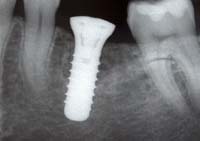

Unter Implantologie in der Zahnheilkunde versteht man das Einbringen von alloplastischen (körperfremden) oder xenogenen (artfremden) Materialien. Seit über 20 Jahren spielen Implantate in der Zahnmedizin eine wichtige Rolle und haben sich allgemein etabliert. Erfolgsaussichten von nahezu 99 Prozent zeigen die rasante positive Entwicklung für die Patienten.

Wir arbeiten in unserer Praxis mit dem bewährten Implantatsystem der

Firma Straumann, einem der größten und bekanntesten Anbieter.